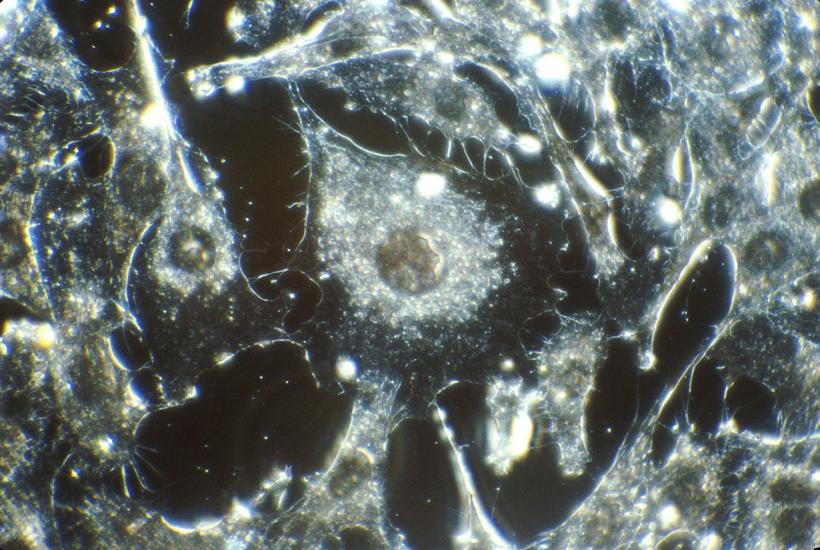

Карцинома (др.-греч. καρκίνος — «рак», -ωμα от ὄγκωμα — «опухоль», дословно — раковая опухоль) — вид злокачественной опухоли (рак), развивающейся из клеток эпителиальной ткани различных органов (кожи, слизистых оболочек и многих внутренних органов).